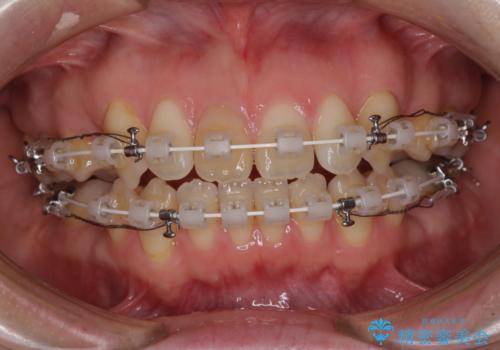

- 矯正装置

- 審美装置

- 治療期間

- 1年9ヶ月

上下の前歯に隙間が空くほど上顎前歯が前に飛び出していましたが、抜歯矯正により上下前歯がぴったりと付くほど口元を引っ込めることができました。